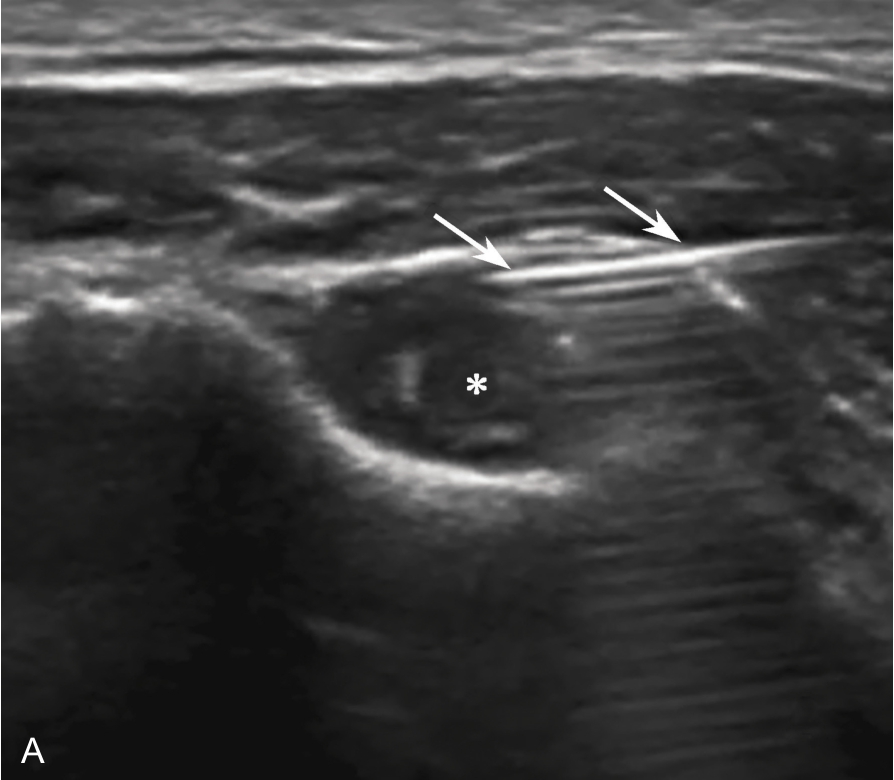

▲ 图2-3-5 超声引导下肱二头肌长头腱鞘介入治疗超声图(二)

A、B.超声引导下平面内进针法,针尖进入腱鞘内;箭头:穿刺针;星号:肌腱